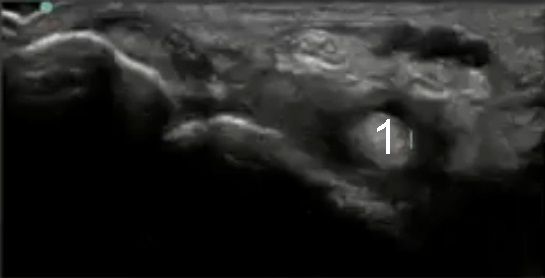

Bild: Fuß und Sprunggelenk, fehlgebildeter Flexor hallucis longus

Musculus flexor hallucis longus